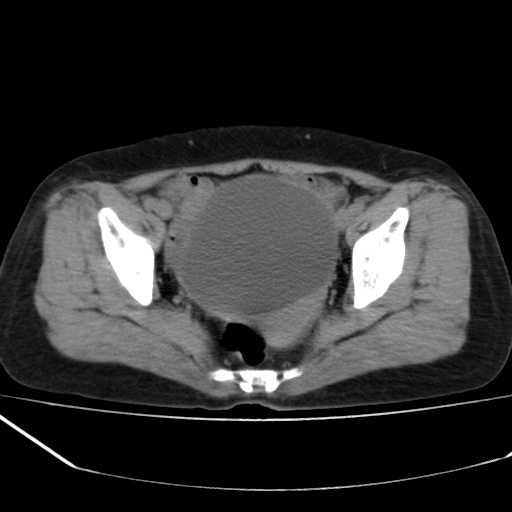

病人不肯增强,是不是膀胱右前方那一个

盆腔右前壁囊性占位,右耻骨轻微骨质吸收.性质选定,建议增扫或病理!!!!!

我只好报盆腔右前壁囊性占位,性质选定,建议增扫或病理.

膀胱右前方占位

病史?临床表现?膀胱右前方囊性占位,边缘光整,考虑良性,建议结合b超检查,既然要做手术,等手术结果吧,只是觉得手术仓促了些。

膀胱右前壁囊性占位,性质难定,要做手术,那就等手术结果吧.